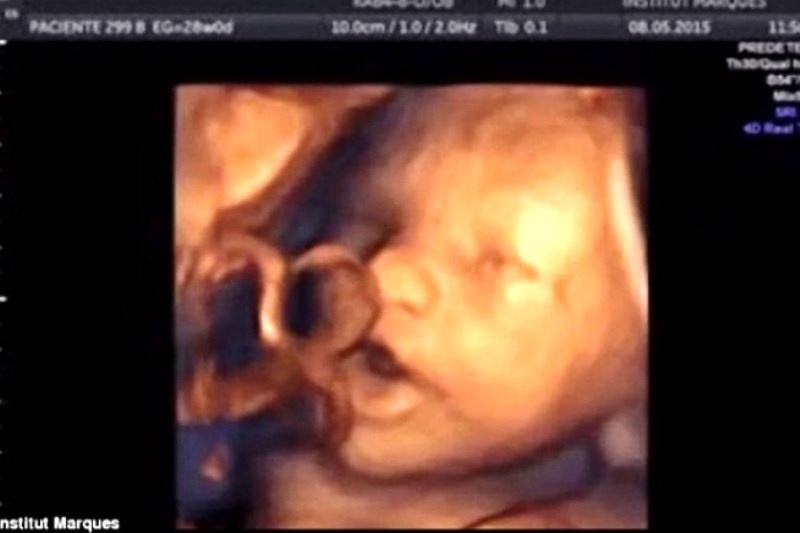

Τα έμβρυα μπορούν να ακούσουν αρκετά καλά από τη 16η κιόλας εβδομάδα της κύησης, αποκαλύπτει μια νέα επιστημονική μελέτη που δημοσιεύεται στην επιθεώρηση Ultrasound.

Για πρώτη φορά στα χρονικά, επιστήμονες από το Ινστιτούτο Marques της Βαρκελώνης κατάφεραν να αποδείξουν ότι ένα έμβρυο μπορεί να ανιχνεύσει τους ήχους και μάλιστα ότι αντιδρά σε αυτούς, κουνώντας το στόμα και τη γλώσσα του.